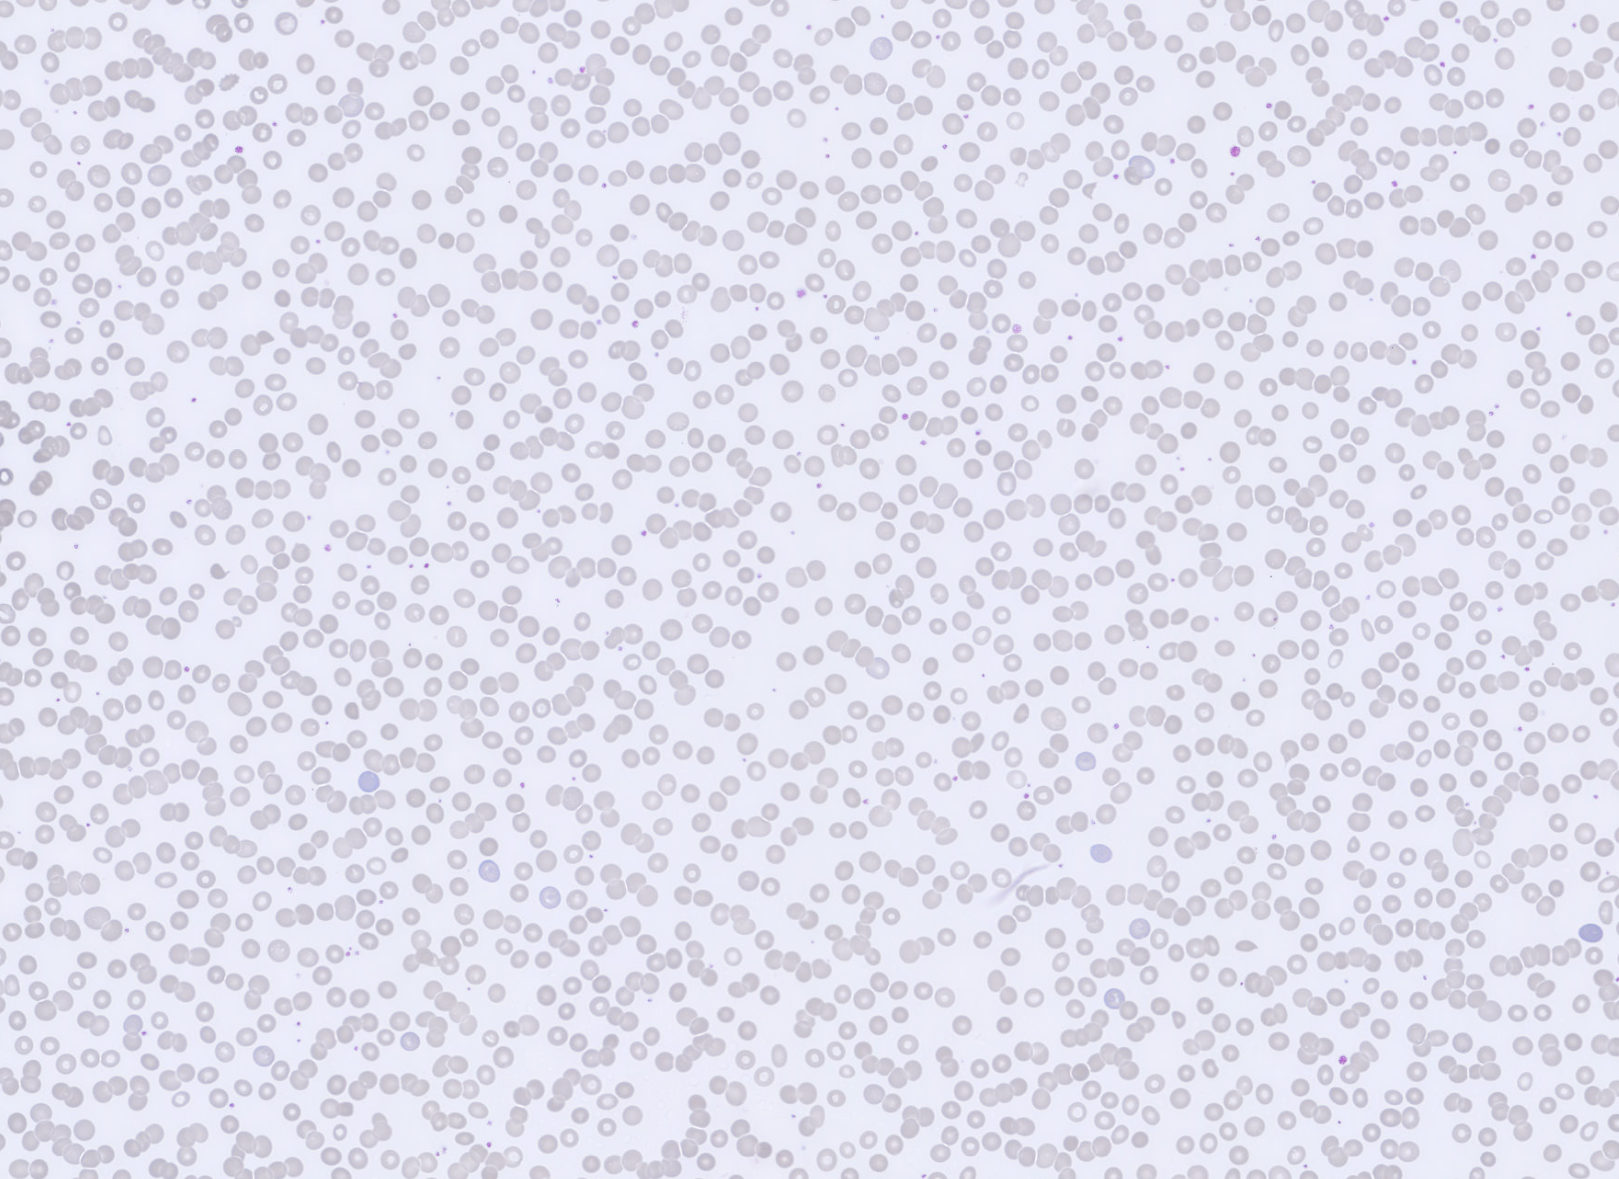

Monthly Cell Challenge #3 2026 RBC overview

Monthly Cell Challenge #3 2026 RBC overview zoom

The erythrocytes are predominantly normocytic and normochromic with relatively uniform morphology. No significant anisocytosis or poikilocytosis is observed. Prominent rouleaux formation is present, with erythrocytes arranged in linear stacks in multiple areas of the smear.